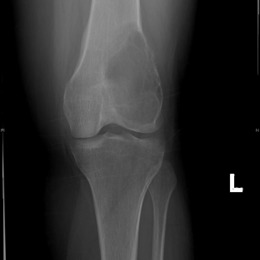

Radiographic imaging is used to help form a diagnosis. These include X-Ray, MRI, CT and Bone Scans.

An example of a Giant Cell Tumor X-Ray is shown.